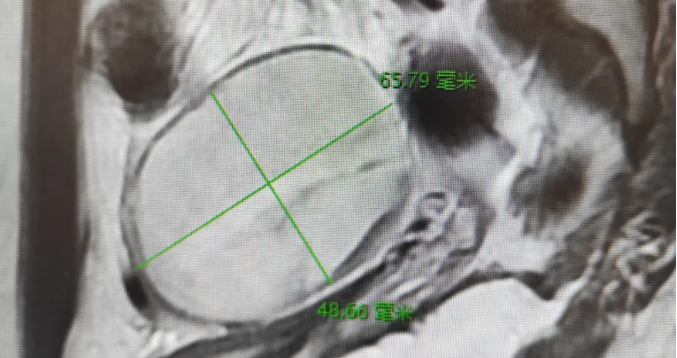

【治疗过程】:蓉蓉因下腹剧痛就医,经医师诊断及各项检查,影像磁共振检查显示盆腔占位,确诊为卵巢囊肿蒂扭转。妇科陈建国主任综合考虑患儿各方面因素后,与家属充分沟通,决定实施 “单孔腹腔镜卵巢囊肿剔除术”。